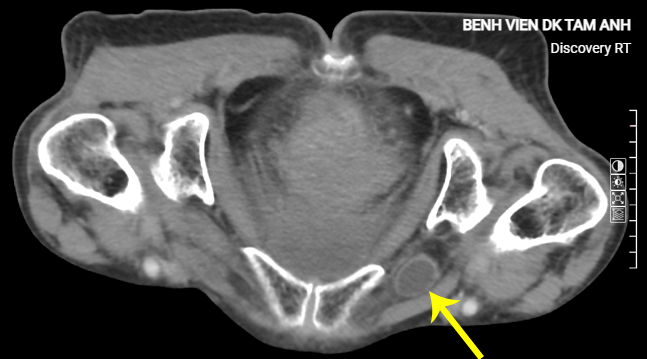

A small bowel loop herniating through the obturator foramen on a CT scan. Tam Anh General Hospital. |

A small bowel loop herniating through the obturator foramen on a CT scan. Tam Anh General Hospital.